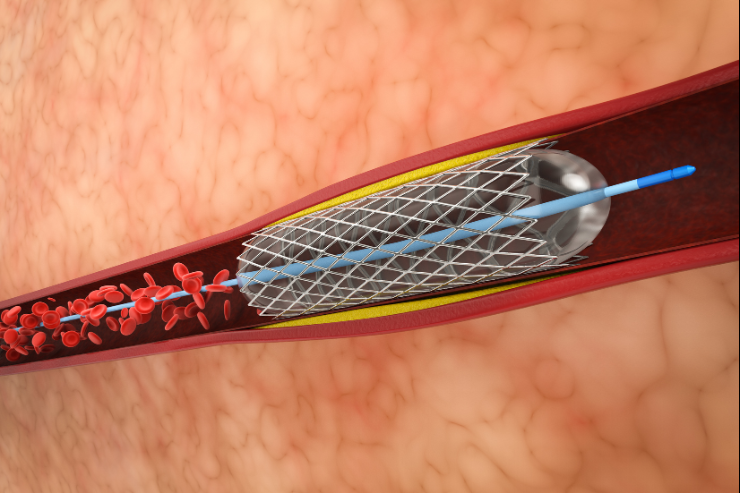

Rotablation

Rotablation is an advanced interventional procedure used to treat heavily calcified and hardened blockages in coronary arteries. It involves a tiny, rotating burr that grinds away tough plaque, creating a smoother path for blood flow. This technique is often used in conjunction with angioplasty and stenting to ensure the arteries are adequately opened, improving heart function and reducing symptoms.

Orbital Atherectomy

Orbital Atherectomy is a specialized procedure used to treat calcified and complex blockages in coronary arteries. It involves a rotating, diamond-coated device that sands down the hardened plaque, improving blood flow. This technique is particularly useful for difficult lesions that are resistant to conventional angioplasty, often used in combination with other interventions to achieve better outcomes.

Renal Angioplasty

Renal Angioplasty is a minimally invasive procedure used to treat narrowed or blocked renal arteries. During the procedure, a balloon is inserted and inflated at the site of the blockage to widen the artery, improving blood flow to the kidneys. This technique helps manage conditions like renal artery stenosis and can reduce symptoms and preserve kidney function.

Peripheral Angioplasty

Peripheral Angioplasty is a minimally invasive procedure designed to treat blockages or narrowing in the peripheral arteries, typically in the legs. A balloon is inserted through a catheter and inflated at the site of the blockage to widen the artery and improve blood flow. This procedure helps alleviate symptoms of peripheral artery disease (PAD) and enhances mobility.